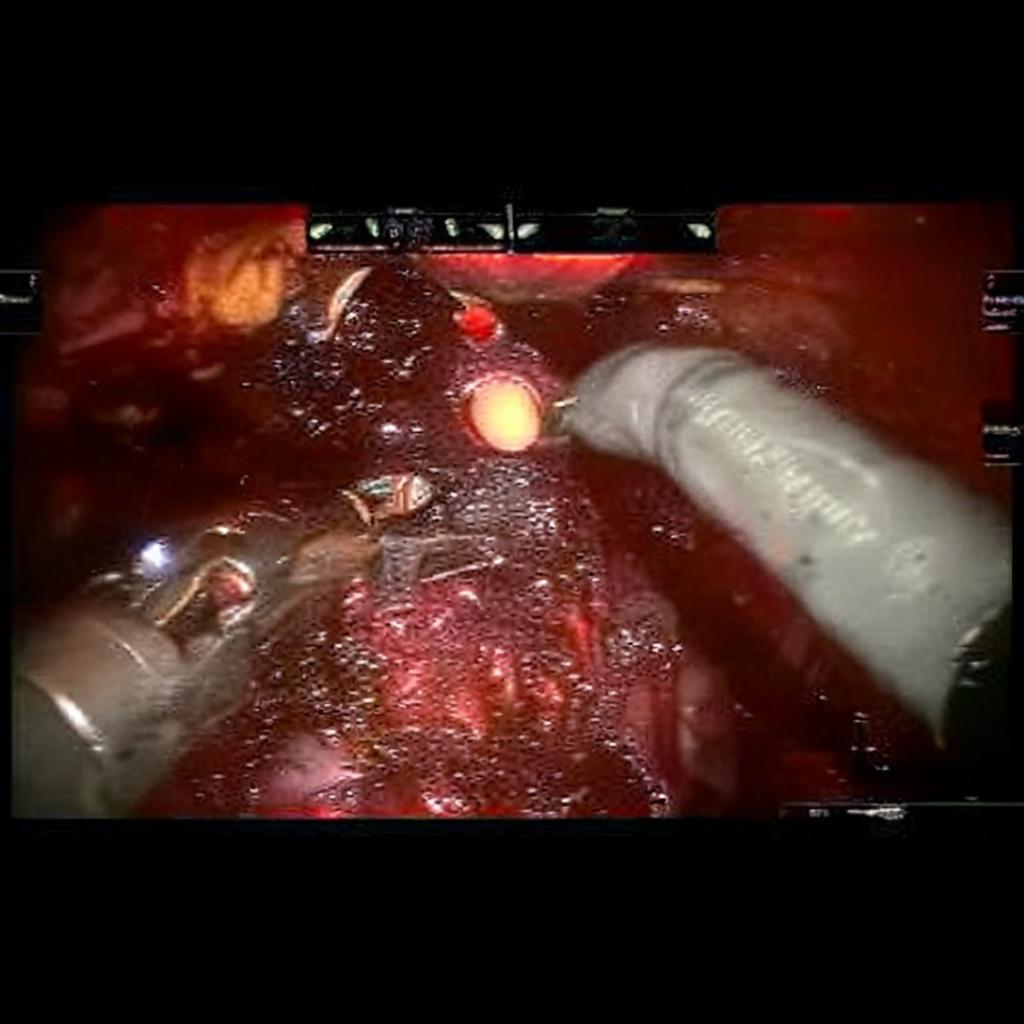

Diffusion models have recently gained significant traction due to their ability to generate high-fidelity and diverse images and videos conditioned on text prompts. In medicine, this application promises to address the critical challenge of data scarcity, a consequence of barriers in data sharing, stringent patient privacy regulations, and disparities in patient population and demographics. By generating realistic and varying medical 2D and 3D images, these models offer a rich, privacy-respecting resource for algorithmic training and research. To this end, we introduce MediSyn, a pair of instruction-tuned text-guided latent diffusion models with the ability to generate high-fidelity and diverse medical 2D and 3D images across specialties and modalities. Through established metrics, we show significant improvement in broad medical image and video synthesis guided by text prompts.

In this work, we focus on the ability of LDMs to generate novel datasets to overcome class imbalances traditionally associated with medical data, and potentially reduce the need for manual annotation of medical 2D and 3D data. We present MediSyn, a pair of text-guided latent diffusion models for broad medical 2D and 3D modality synthesis. To overcome the scarcity of labelled medical data, we leverage a vast corpus of more than 5 million image-caption pairs and 100,000 video-caption pairs collected from the public domain across numerous medical specialties, and integrate comprehensive natural language annotations to develop a pair of versatile diffusion models for the medical domain.

For Medisyn 3D, we compiled a total of 107,216 medical video-caption pairs, spanning 2 specialties and 3 imaging modalities. We performed model evaluation on a separate set of 200 pairs (100 from each specialty). Summary statistics for the entire dataset is provided in Table 1.

| General Surgery | 2,150,757 |

| Surgical Footage | 2,150,757 |

3.4 Video Generation

Video synthesis is notably more difficult than image synthesis primarily due to the need for both spatial and temporal coherence [37]. To help overcome this, we proceed with HiGen, a text-to-video LDM that decouples spatial and temporal processing across two distinct stages: structure and content [38]. HiGen incorporates a Variational Autoencoder (VAE) for encoding and decoding frames, a 3D U-Net for noise estimation (synthesis), and a frozen CLIP encoder for embedding textual prompts. In the structure phase, the U-Net incorporates the middle frames of the videos as spatial priors, alongside the corresponding embedded texts. To further increase temporal consistency, the content level introduces embeddings of motion and appearance variations from the corresponding videos. Motion vectors are derived from pixel-wise differences between consecutive frames, while appearance values are obtained from the image encoder of DINOv2 [39].

Our findings demonstrate Medisyn’s remarkable ability to generate high-fidelity and diverse medical images, image sequences and volumetric scans across various medical subspecialties and imaging modalities. Other medical text-driven diffusion models, such as TauPETGen [42] for tau PET images and GenerateCT [43] for chest CT volumes, have proven successful in generating high-quality images that accurately depict anatomical features and clinical conditions. However, these models are constrained to a single imaging modality and anatomical region, thereby restricting their applicability. Moreover, they were trained on relatively small datasets sourced from a limited number of institutions, which could lead to more biased outputs. In contrast, Medisyn, having been trained on one of the largest publicly accessible medical image and video datasets to date, is equipped to synthesize data that cover numerous medical disciplines, population groups, and disease states. Leveraging our two models, we can synthesize new medical datasets as well as augment existing ones, potentially improving a wide array of medical machine learning tools, both general and specialized. Additionally, our models can minimize the need to repeatedly fine-tune on specific datasets for generating different imaging modalities, thus reducing computational costs for academic labs.

In summary, we introduced a pair of text-conditional LDMs trained on an extensive medical image and video dataset covering various medical subspecialties and imaging modalities. By generating high-fidelity and diverse medical 2D and 3D images, Medisyn illustrates the potential for a singular framework to broadly address the challenge of data scarcity in healthcare.